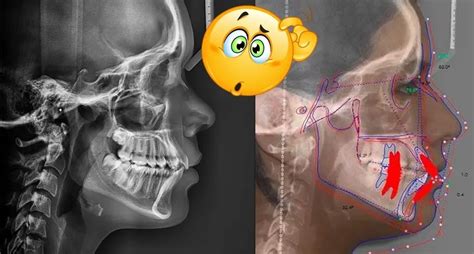

En la radiografía vemos como la posición de los dientes y del proceso alveolar que hemos conseguido otorga un equilibrio a las estructuras faciales. Observamos también como los tejidos blandos descansan con un equilibrio perfecto sobre las estructuras internas.

El resultado es el de unas proporciones faciales perfectas en labios, nariz y mentón; una relación correcta entre la nariz y el maxilar superior y una correcta relación entre el maxilar superior e inferior.